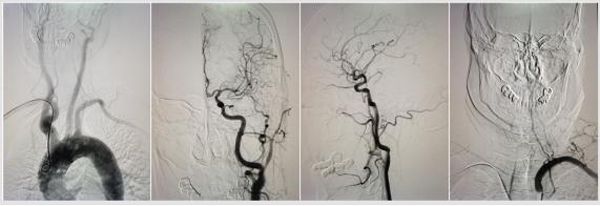

目前,二一五医院神内一病区已顺利完成4例患者的经桡动脉造影,无一例血管痉挛或并发症发生,术后即刻患者可下地活动,患者及家属反应良好。下图为另3位患者经桡动脉造影图。